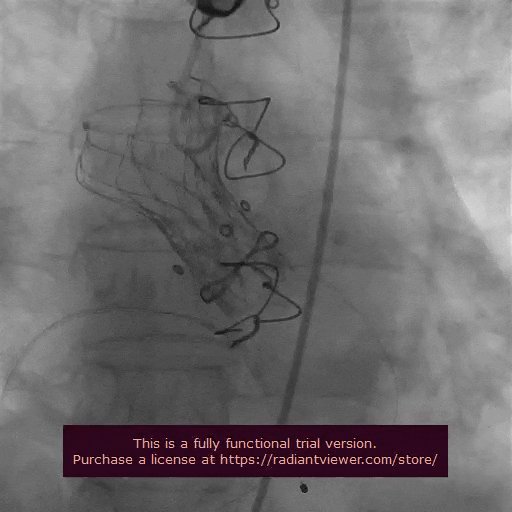

术中精彩操作

主动脉根部造影

瓣膜初始定位

瓣膜释放到2/3,造影确认位置合理

完全释放后造影评估